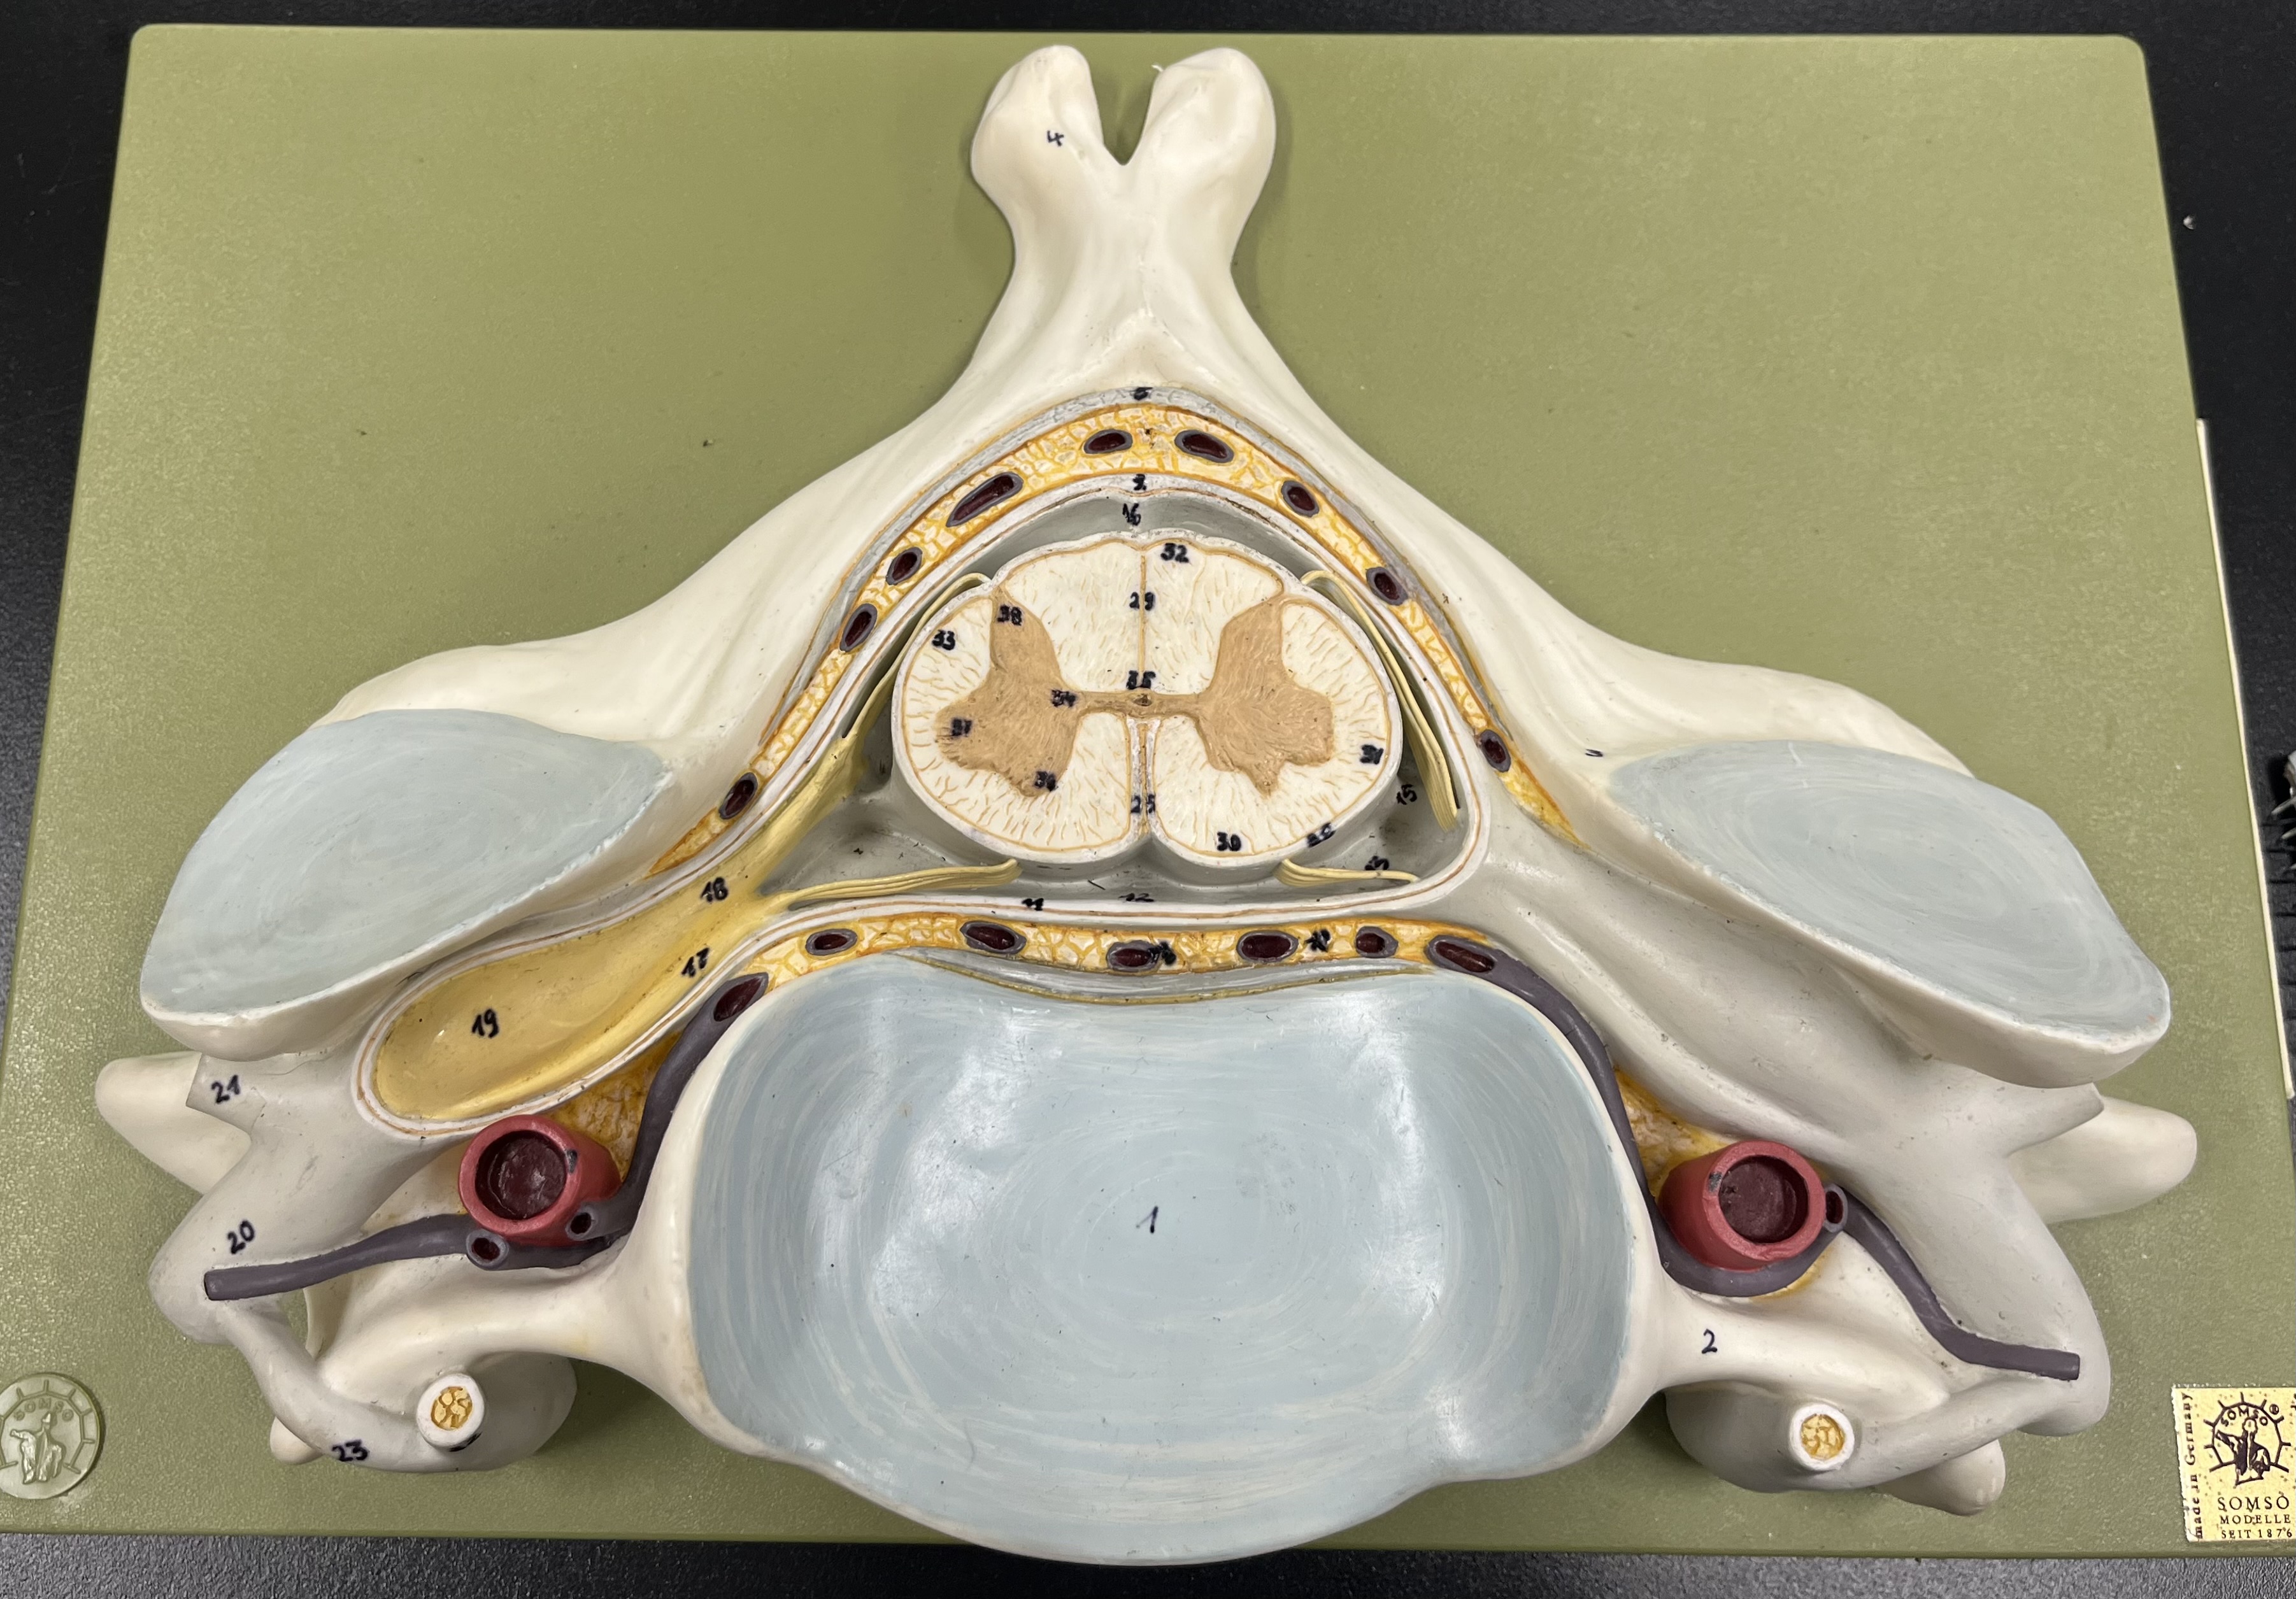

epidural space

dura mater

subdural space

arachnoid mater

subarachnoid space

pia mater

denticulate ligaments

What is the groove here?

anterior median fissure

posterior median sulcus

posterior (dorsal) horn

posterior (dorsal) horn; R—>L

anterior (ventral) horn

lateral horn (selected models)

gray commissure

central canal

anterior column

lateral column

posterior column

white commissure

posterior (dorsal) root ganglion

What is the bulb here?

posterior (dorsal) root ganglion

posterior (dorsal) root

posterior (dorsal) root

anterior (ventral) root

anterior (ventral) root

dorsal ramus

dorsal ramus

ventral ramus

ventral ramus

rami communicantes

rami communicantes

sympathetic chain ganglia

sympathetic chain ganglia